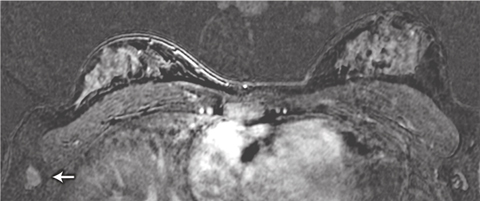

We identified two patients with lesions potentially putting them at higher risk of breast cancer and one with metastatic cancer in an axillary lymph node. The lymph node metastasis was not initially identified in the MRI scan: the patient palpated the node herself 1 month after imaging was done, and when the MRI scan was viewed retrospectively, the metastasis was in fact visible (Box 5). The patient’s imaging occurred early in the study, and failure to detect the cancer was the result of inexperience in interpreting breast MRI scans at that stage. This underlines the importance of carrying out breast MRI examination and reporting in centres that have expert multidisciplinary experience in breast surveillance, including MRI.